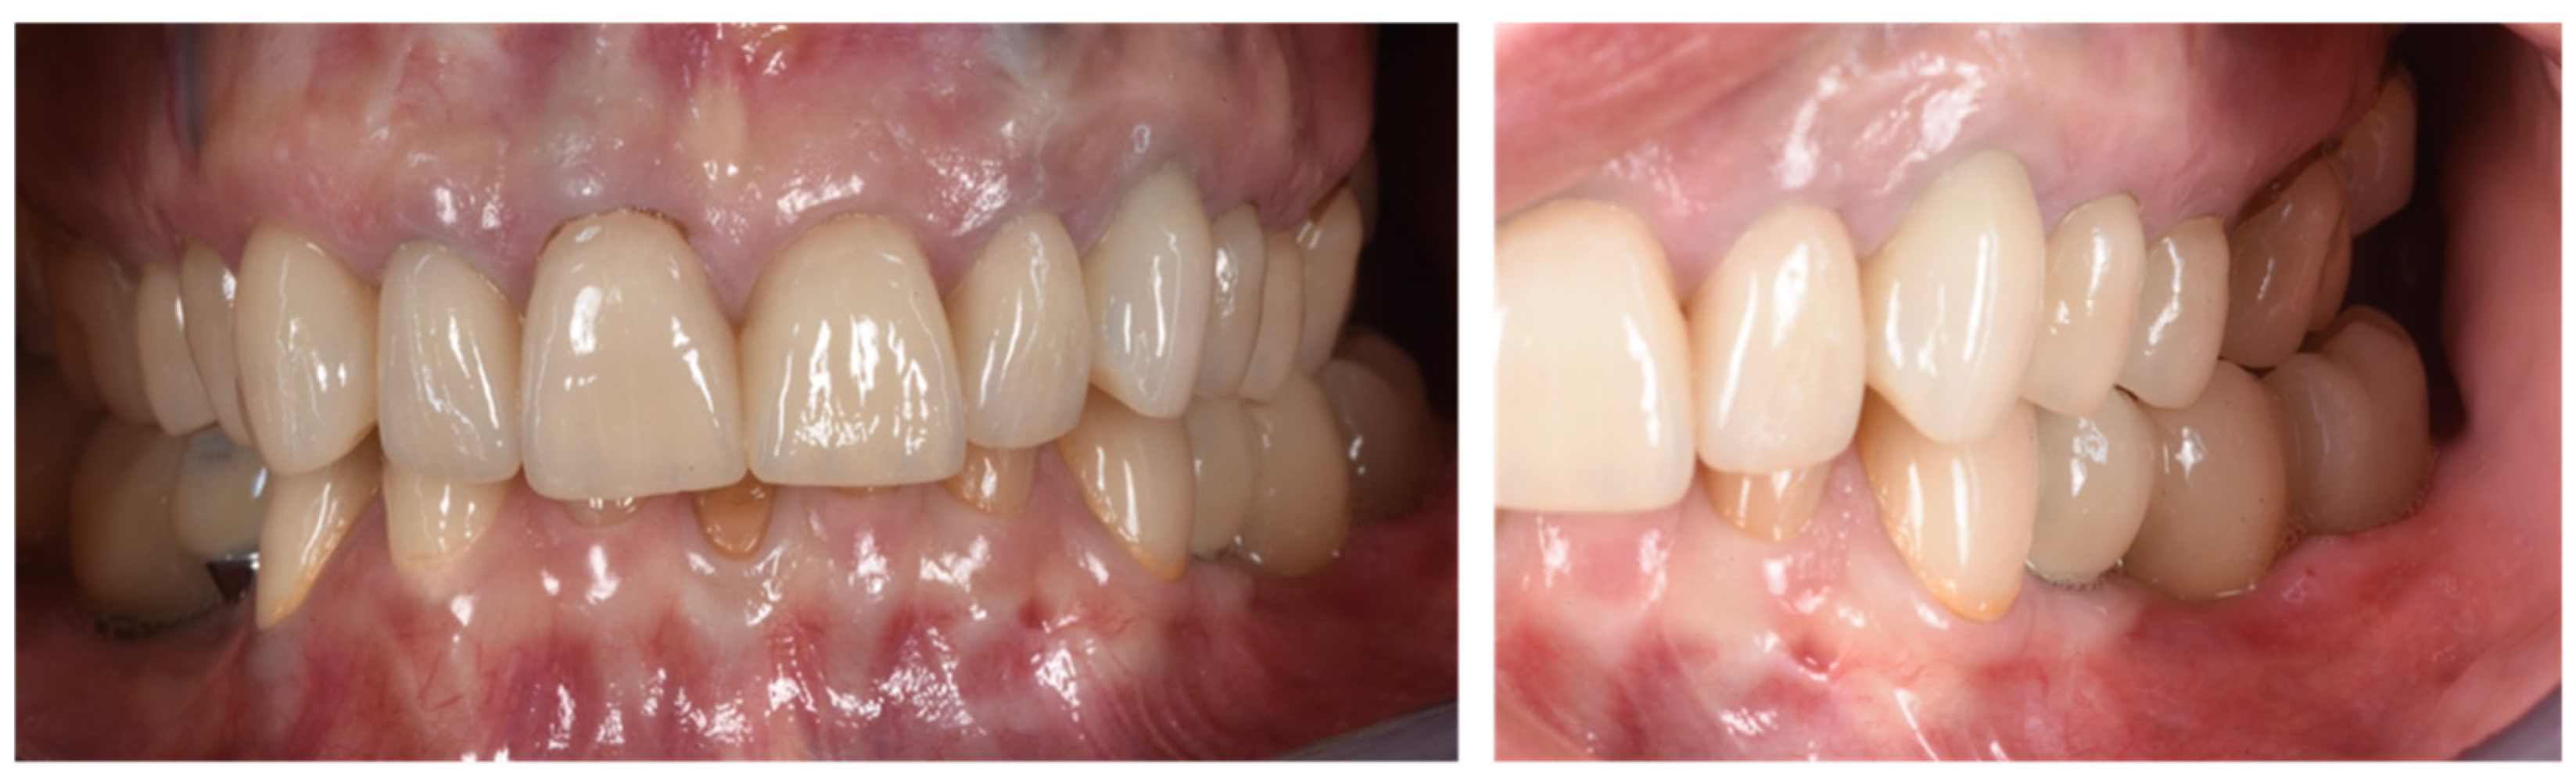

Figure 10.

Clinical evaluation after 18 months of prosthetic loading.

Figure 11.

Scan taken after 18 months of prosthetic loading.